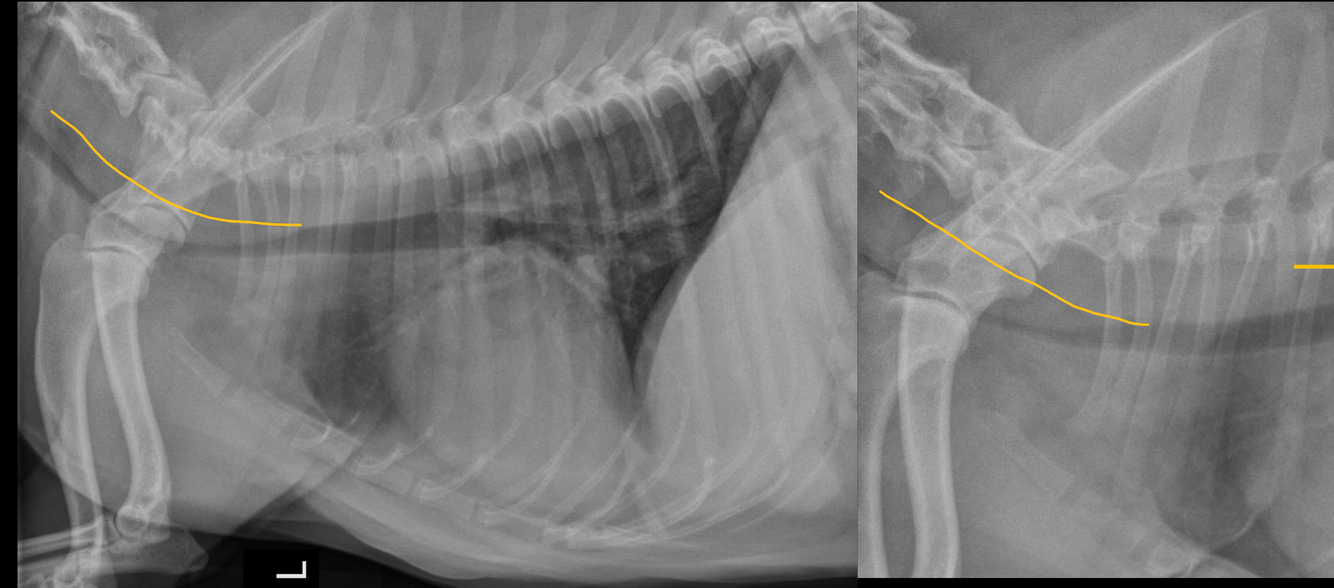

What is seen in these thoracic radiographs?

A

• sternal lysis and collapse with soft tissue swelling

• multiple, small pulmonary nodules

• osteolytic diaphysis and osteophyte formation